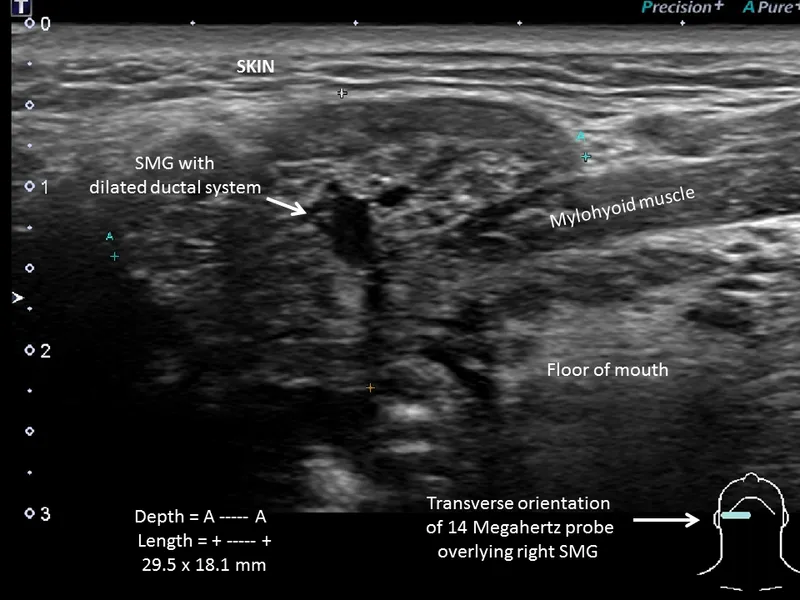

- Ultrasound (USG): initial imaging of choice; shows inflammation, abscess, stones, duct dilation.